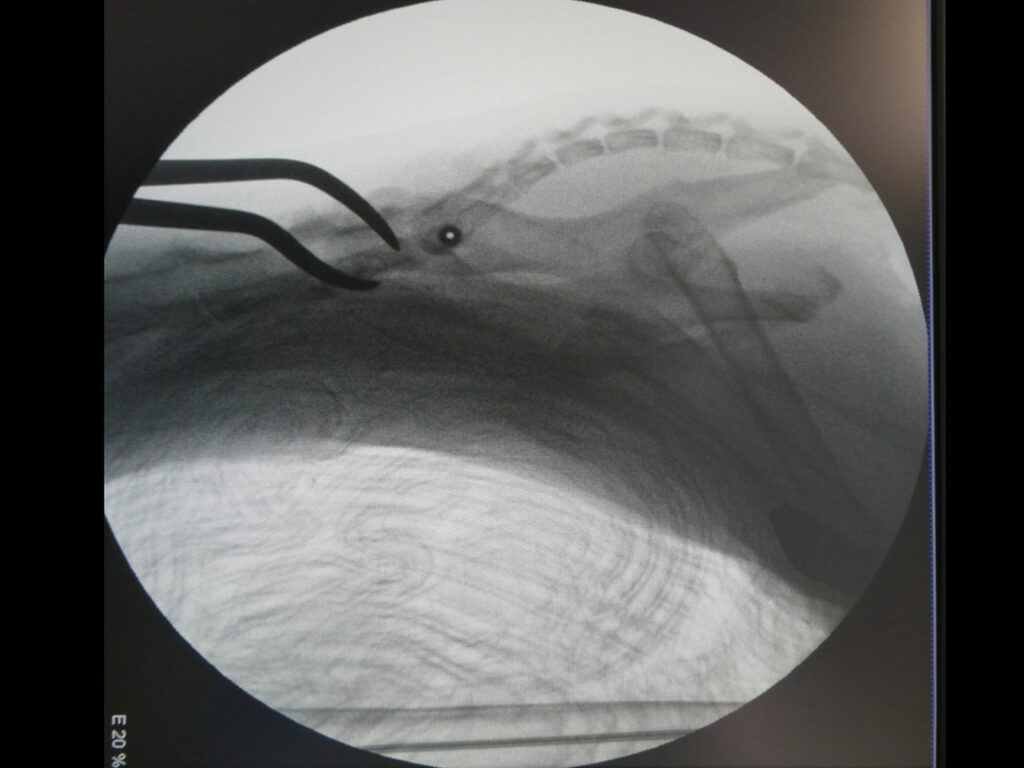

Réduction d’une luxation sacro-iliaque sur un chat par voie mini invasive. Une sis canulée est introduite de manière percutanée avec une ouverture minimale.